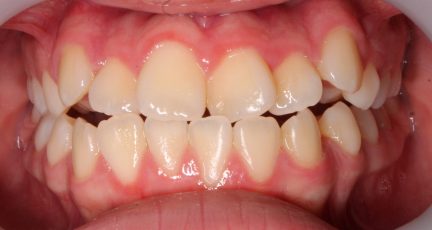

État initial

- Relation de classe I obtenue

- Guidage fonctionnel des canines des deux côtés

- Articulé antérieur corrigé

- Articulé postérieur corrigé

- Surplomb et recouvrement normaux obtenus

- Lignes médianes coïncidentes

- Bonne inclinaison axiale des incisives

- Alignement des deux arcades par dérotation

- Forme de l'arcade améliorée

- La ligne de sourire esthétique a été obtenue